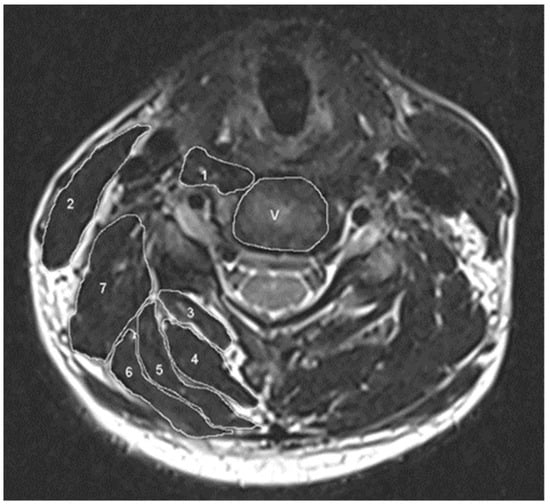

2.2. Radiographic Assessment